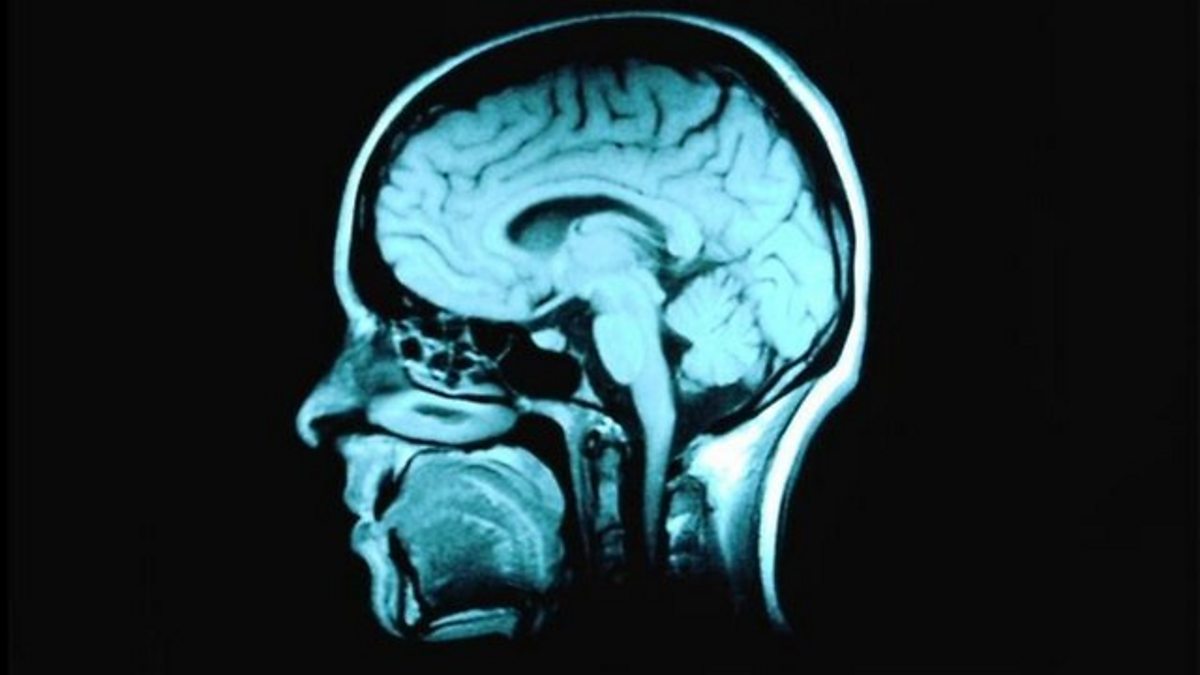

'New ideas' to treat brain tumours

Susan Short and Ed Jones discuss potential new treatments for brain tumours.